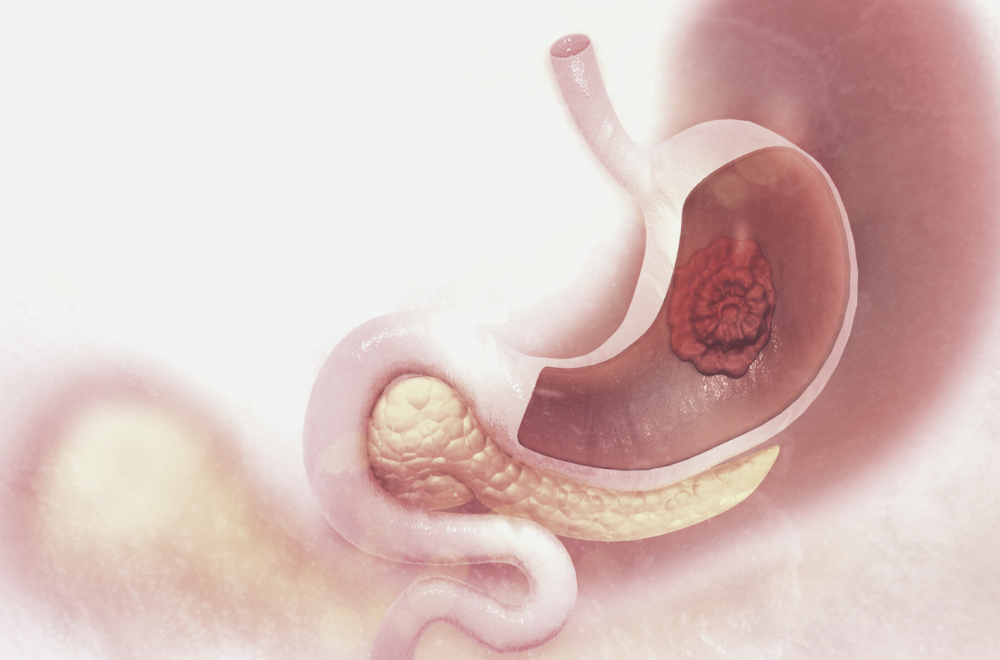

Гастроинтестинальные стромальные опухоли

Гастроинтестинальные стромальные опухоли (ГИСО) развиваются из клеток соединительной ткани, относятся к группе сарком. ГИСО могут развиться в стенках пищеварительного тракта (от пищевода и до ануса), но чаще всего локализованы в желудке или тонкой кишке.

Рак желудка

Рак желудка — злокачественная опухоль, которая образуется из клеток слизистой органа.